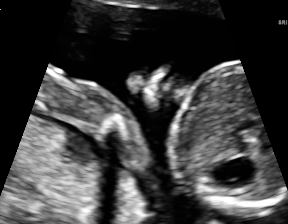

IV-D Experiments on cross-device fetal US

The previous experiment on fetal US images is supported by data restricted to one US imaging device. Here, we evaluate MIDNet for a standard plane classification task on data from different imaging devices (different device domains). Device A is “GE Voluson E8” which is the same device in Sec. IV-C, which acquired 2D fetal US images. Device B is “Philips EPIQ V7 G” which acquired another images sampled from about 500 2D US examinations with gestational ages between 20-32 weeks (see Fig. 2 (b)). In this experiment, we use four different anatomical standard plane locations with sufficient images in both domains, including Abdominal, Brain, Femur and Lips, which are selected by an 10-year-experienced sonographer. In this experiment, the source domain is set as device A while the target domain is device B. Training data consists of all four standard planes from the source domain as well as Abdominal and Brain from the target domain. We aim to separate anatomical features (categorical features) and imaging device features (domain features) to obtain generalized anatomical features for achieving high performance of standard plane classification on (Femur and Lips). Here, contains Abdominal, Brain, Femur and Lips from the source domain and contains Abdominal and Brain from the target domain. Hyper-parameters to in Eq. 11 are for the proposed MIDNet model and is additionally for MIDNet+.

We further present correctly classified and mis-classified examples of using MIDNet in Fig. 11 (b).